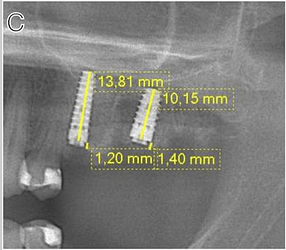

Case photos below provided by Rehberger Bescós F, Salgado Peralvo ÁO, Chamorro Petronacci CM, Chele D, Camacho Alonso F, Peñarrocha Oltra D, Lado Baleato Ó, Pérez Sayáns M. [Marginal bone loss and associated factors in immediate dental implants: a retrospective clinical study.](Marginal bone loss and associated factors in immediate dental implants: a retrospective clinical study - PMC)

Measurements for the calculation of the MBL performed: A Preoperative evaluation; B immediate postoperative period; C 2 months after placement of the implants; D 36 month follow-up

A BL example in IDI #33 (A1: March 2019- A2: September 2023); B BR example in IDI #26 (B1: November 2019- B2: January 2020); C BO example in IDI #46 (C1: January 2019-C2 January 2020)

The present study supports the clinical efficacy of immediate implant placement protocol with high survival rates and acceptable MBL. Regarding the latter, the insertion of implants bone level about 3 mm infracrestal should be considered to ensure a subcrestal implant platform position during bone remodeling during the first months after implantation. The insertion of immediate implants in the jaw compared to the maxilla, the abutment height and rotational abutments demonstrated a positive impact over the MBL.